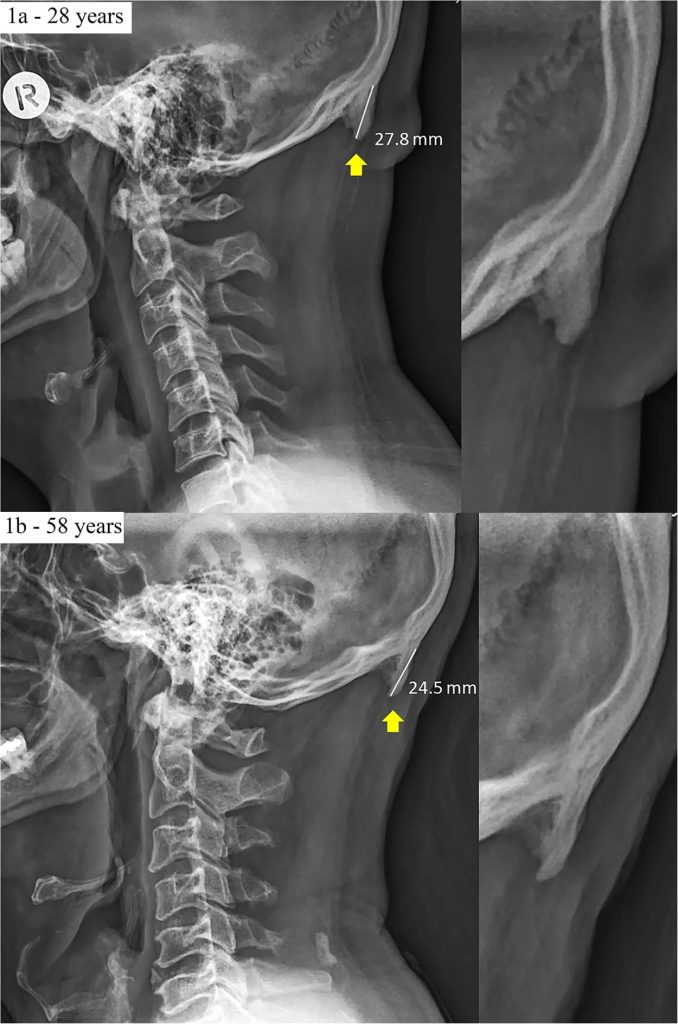

Es decir, la forma del uso de los móviles celulares y su frecuencia ha empezado a modificar el esqueleto y no solo ha alterado comportamientos sociales. El descubrimiento de la llamada “protuberancia occipital externa” ha comenzado a ser creciente desde el 2016 en radiografías a adolescentes, pero los rayos X han confirmado que esto también afecta a los adultos.

El abultamiento en punta, llamado también «protuberancia occipital externa», se encuentra en la parte posterior del cráneo, justo arriba del cuello.

Este trabajo lleva el título traducido “La exostosis prominente que se proyecta desde la escama occipital es más importante y prevalente en adultos jóvenes que en los grupos de mayor edad”.

En la publicación hay gráficas que comparan el impacto de esto en dos diferentes grupos, según la edad: